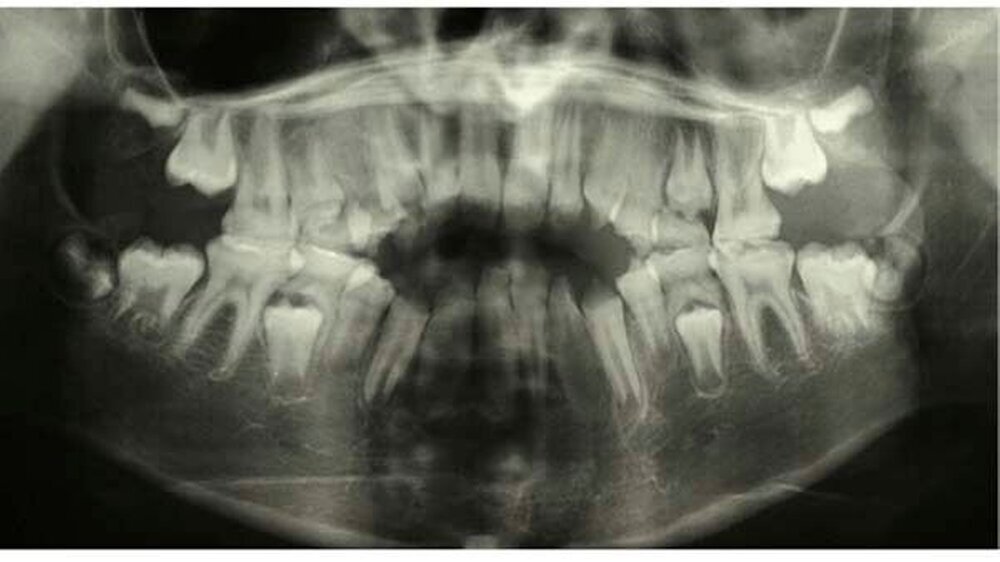

Im radiologischen Befund konnte teilweise ein Kontrast zwischen Schmelz und Dentin festgestellt werden, jedoch war bei beiden Dentitionen eine verminderte Schmelzdicke ersichtlich (Abbildung 4). Auf Grund der radiologischen und klinischen Beurteilung konnte die Diagnose Amelogenesis imperfecta generalisata vom hypoplastischen Typ gestellt werden.